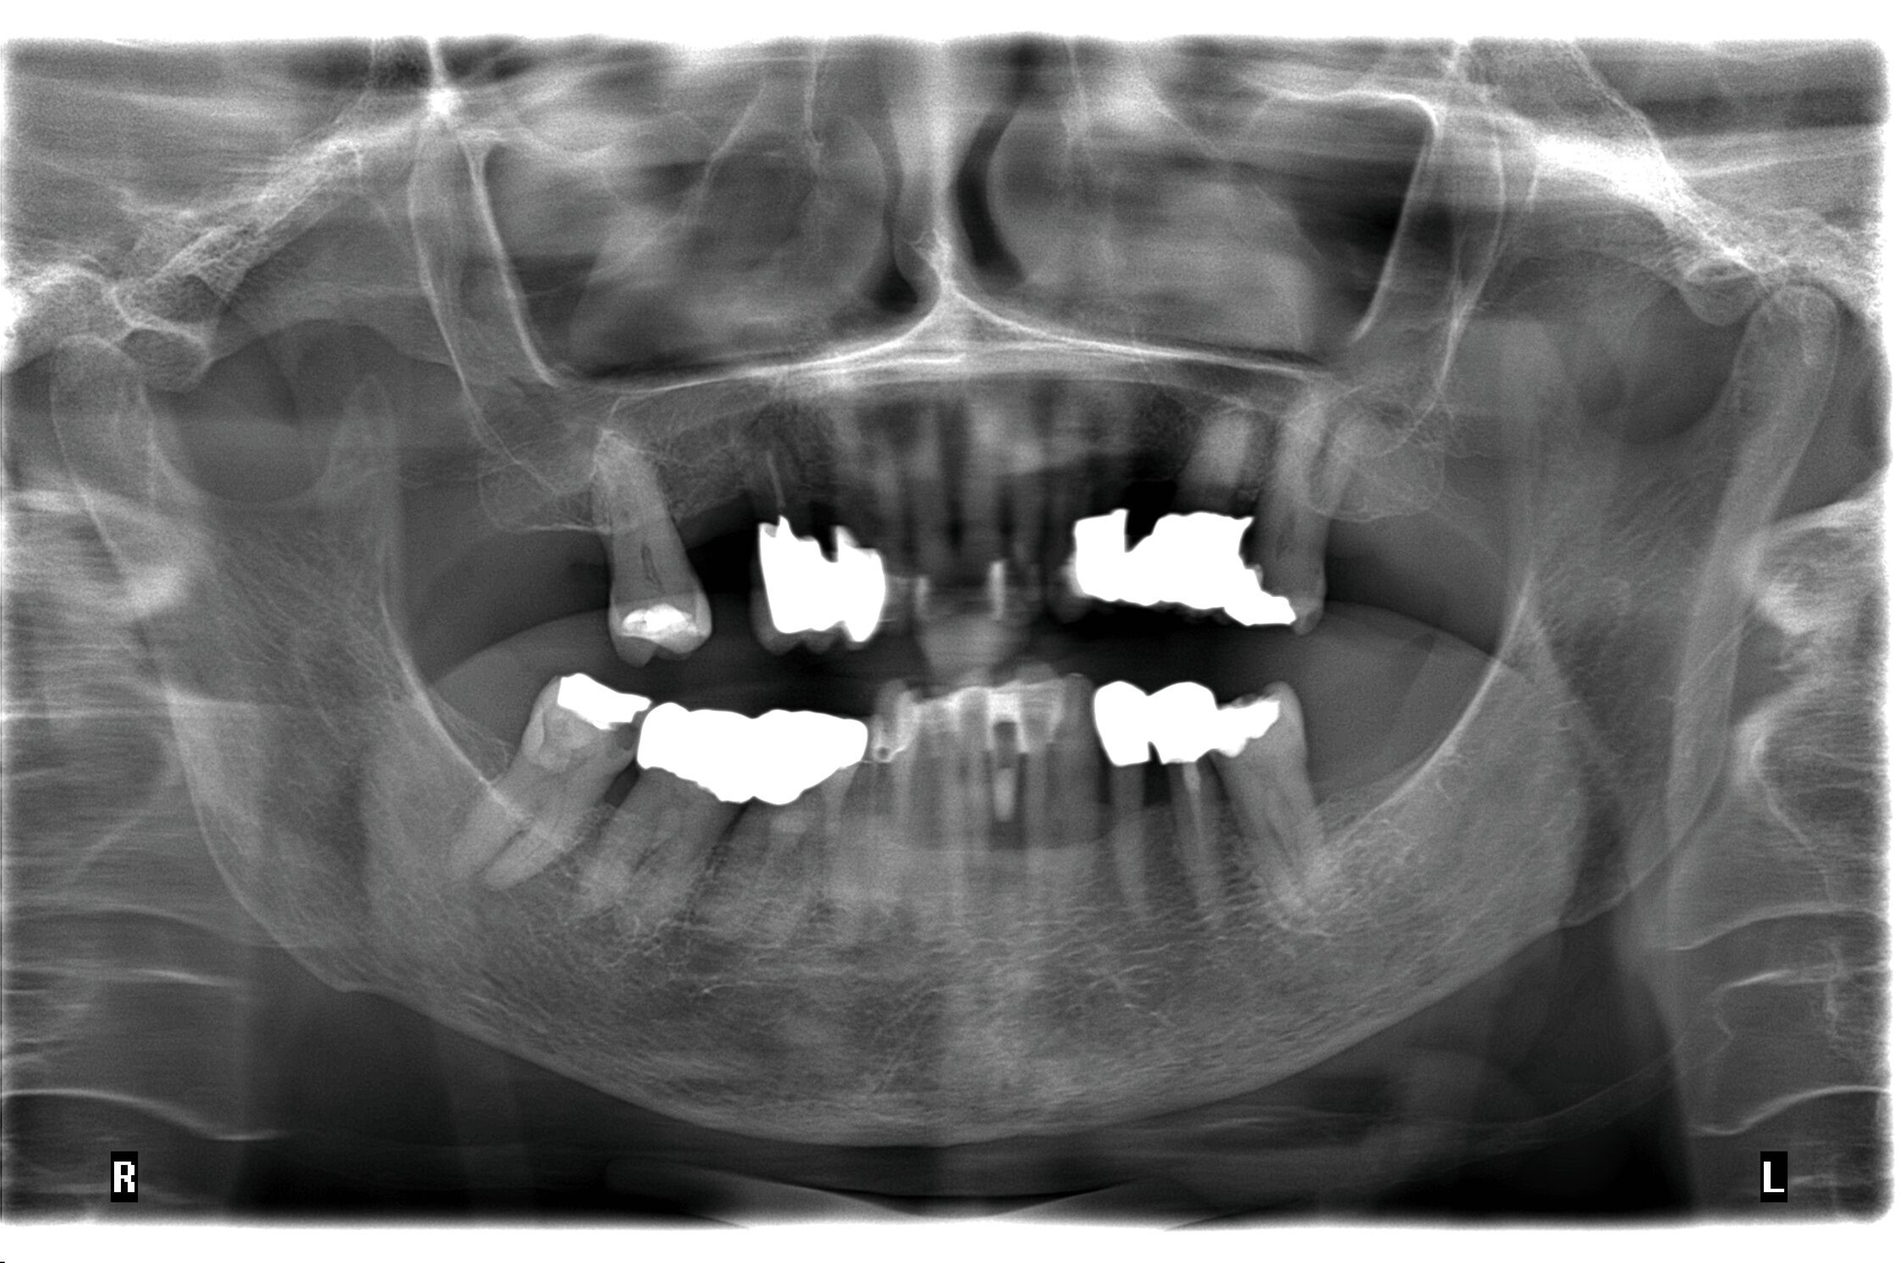

Die hochbetagte Patientin war bereits viele Jahre in der Poliklinik für Zahnerhaltung des Universitätsklinikums Tübingen zahnmedizinisch betreut worden, allerdings aus Sorge vor einer Corona-Infektion von Ende 2019 bis August 2023 knapp vier Jahre der zahnärztlichen Versorgung ferngeblieben. Grund der Wiedervorstellung war dann ein wenige Tage zuvor stattgefundener Füllungsverlust am Zahn 36. Hier bemerkte die Patientin eine an der Zunge störende scharfkantige Fraktur des Molaren (Abbildungen 2 und 3). Weitere Schmerzen oder Beschwerden gab sie nicht an. Im Rahmen der zahnärztlichen Untersuchung konnten multiple Rezessionen und diverse arretierte Brown-Spot-Läsionen festgestellt werden.

Obwohl die unterstützende Parodontitistherapie (UPT) vier Jahre unterbrochen war, konnte bis auf einen Grad III gelockerten Zahn 31 und eine Grad I–II gelockerte, restliche Unterkieferfrontbezahnung ein gut erhaltenes Gebiss festgestellt werden. Dies ist auch darauf zurückzuführen, dass die Patientin – trotz ihres fortgeschrittenen Alters – die häusliche Mundhygiene stets sehr gründlich betrieb, wie auch aus früheren Akteneinträgen ersichtlich wurde (Abbildung 4).